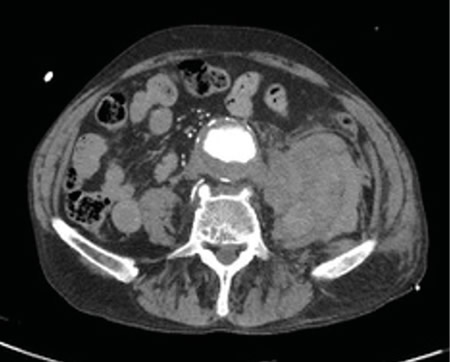

Figura 2

La rotura de aneurisma de aorta supone el síntoma principal en hasta un 25 % de los casos de la patología de aneurisma de aorta, que constituye una entidad potencialmente mortal. También puede aparecer con menor prevalencia como lumbalgia, coxalgia e, incluso, gonalgia, no comentándolo como dolor vertebral o neuropático, sino como irritación a nivel de psoas ilíaco como primera sintomatología.

Se estima que solo en un 50 % de los casos aparece la triada clásica del aneurisma, por lo que es necesario tener un alto nivel de alerta para sospecharlo, ya que la hipovolemia puede estar contenida por un hematoma peritoneal.